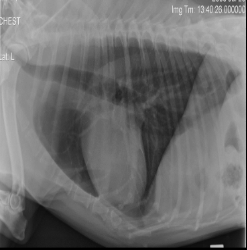

What sign is this?

Bacpack sign - L. atrial enlargement